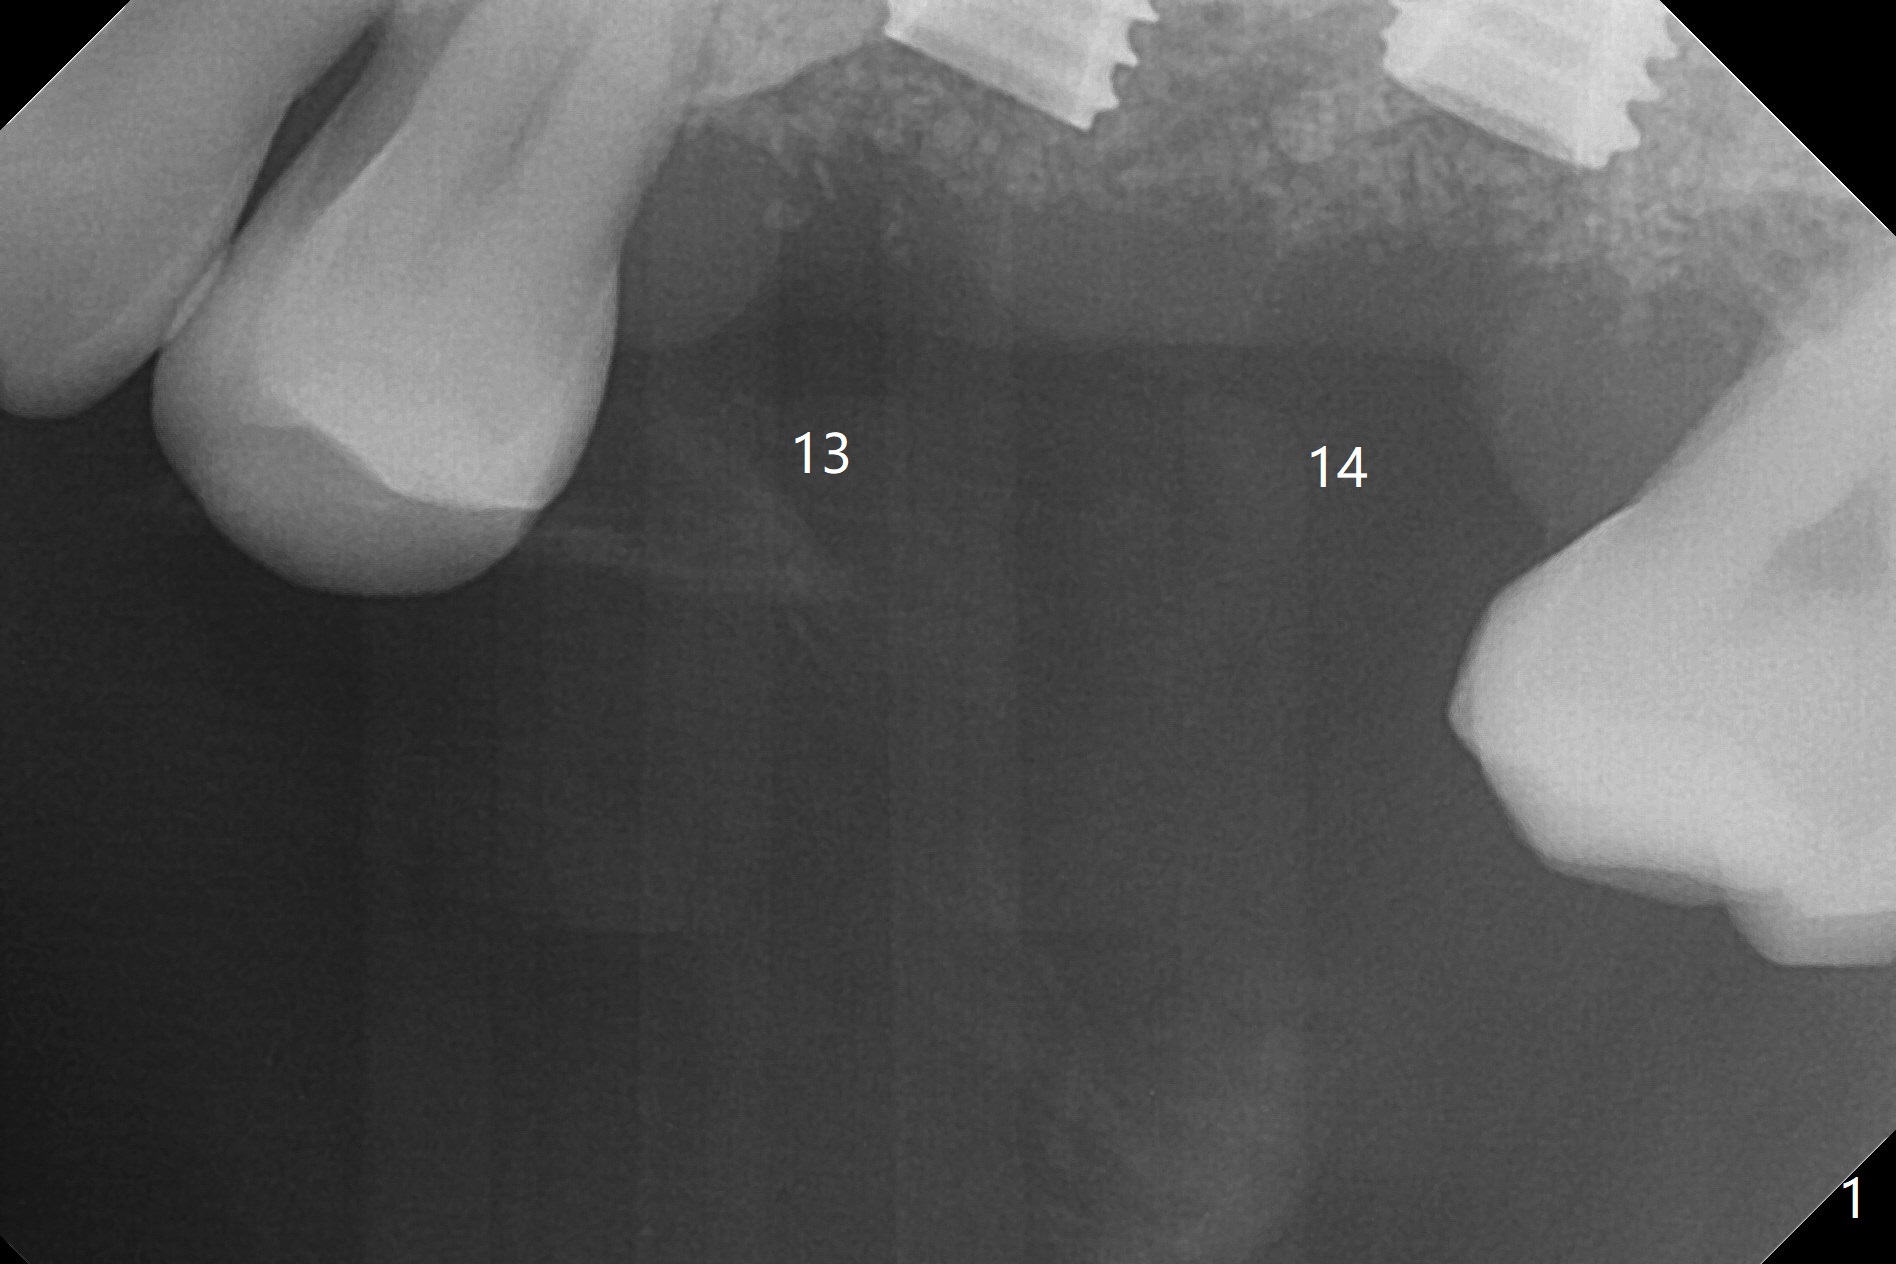

After placement of a 4.5x8.5 mm implant at #13, a vertical anchor pin is used, which is helpful for #14 osteotomy (Fig.1-3). One hand is free. Sinus lift with 2.8 mm reamer is not efficient, since it is difficult to feel stopper. A 5x7.3 mm implant has to be removed from the site of #14 for use of Magic Expanders from 3.0 to 4.3 mm at the depth of 13 mm (gingival level). Autogenous bone harvested from osteotomy is used for sinus lift. It appears that the implants are placed deep; healing abutments with 5 mm cuff are placed (Fig.4 (extraoral bitewing)).